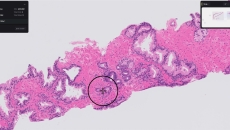

ArteraAI Prostate analyzes digital pathology images of a prostate cancer biopsy slide to help clinicians predict long-term outcomes.

Paige Prostate analyzes digitized biopsy slides and identifies areas that could be cancerous for the pathologist to review further.